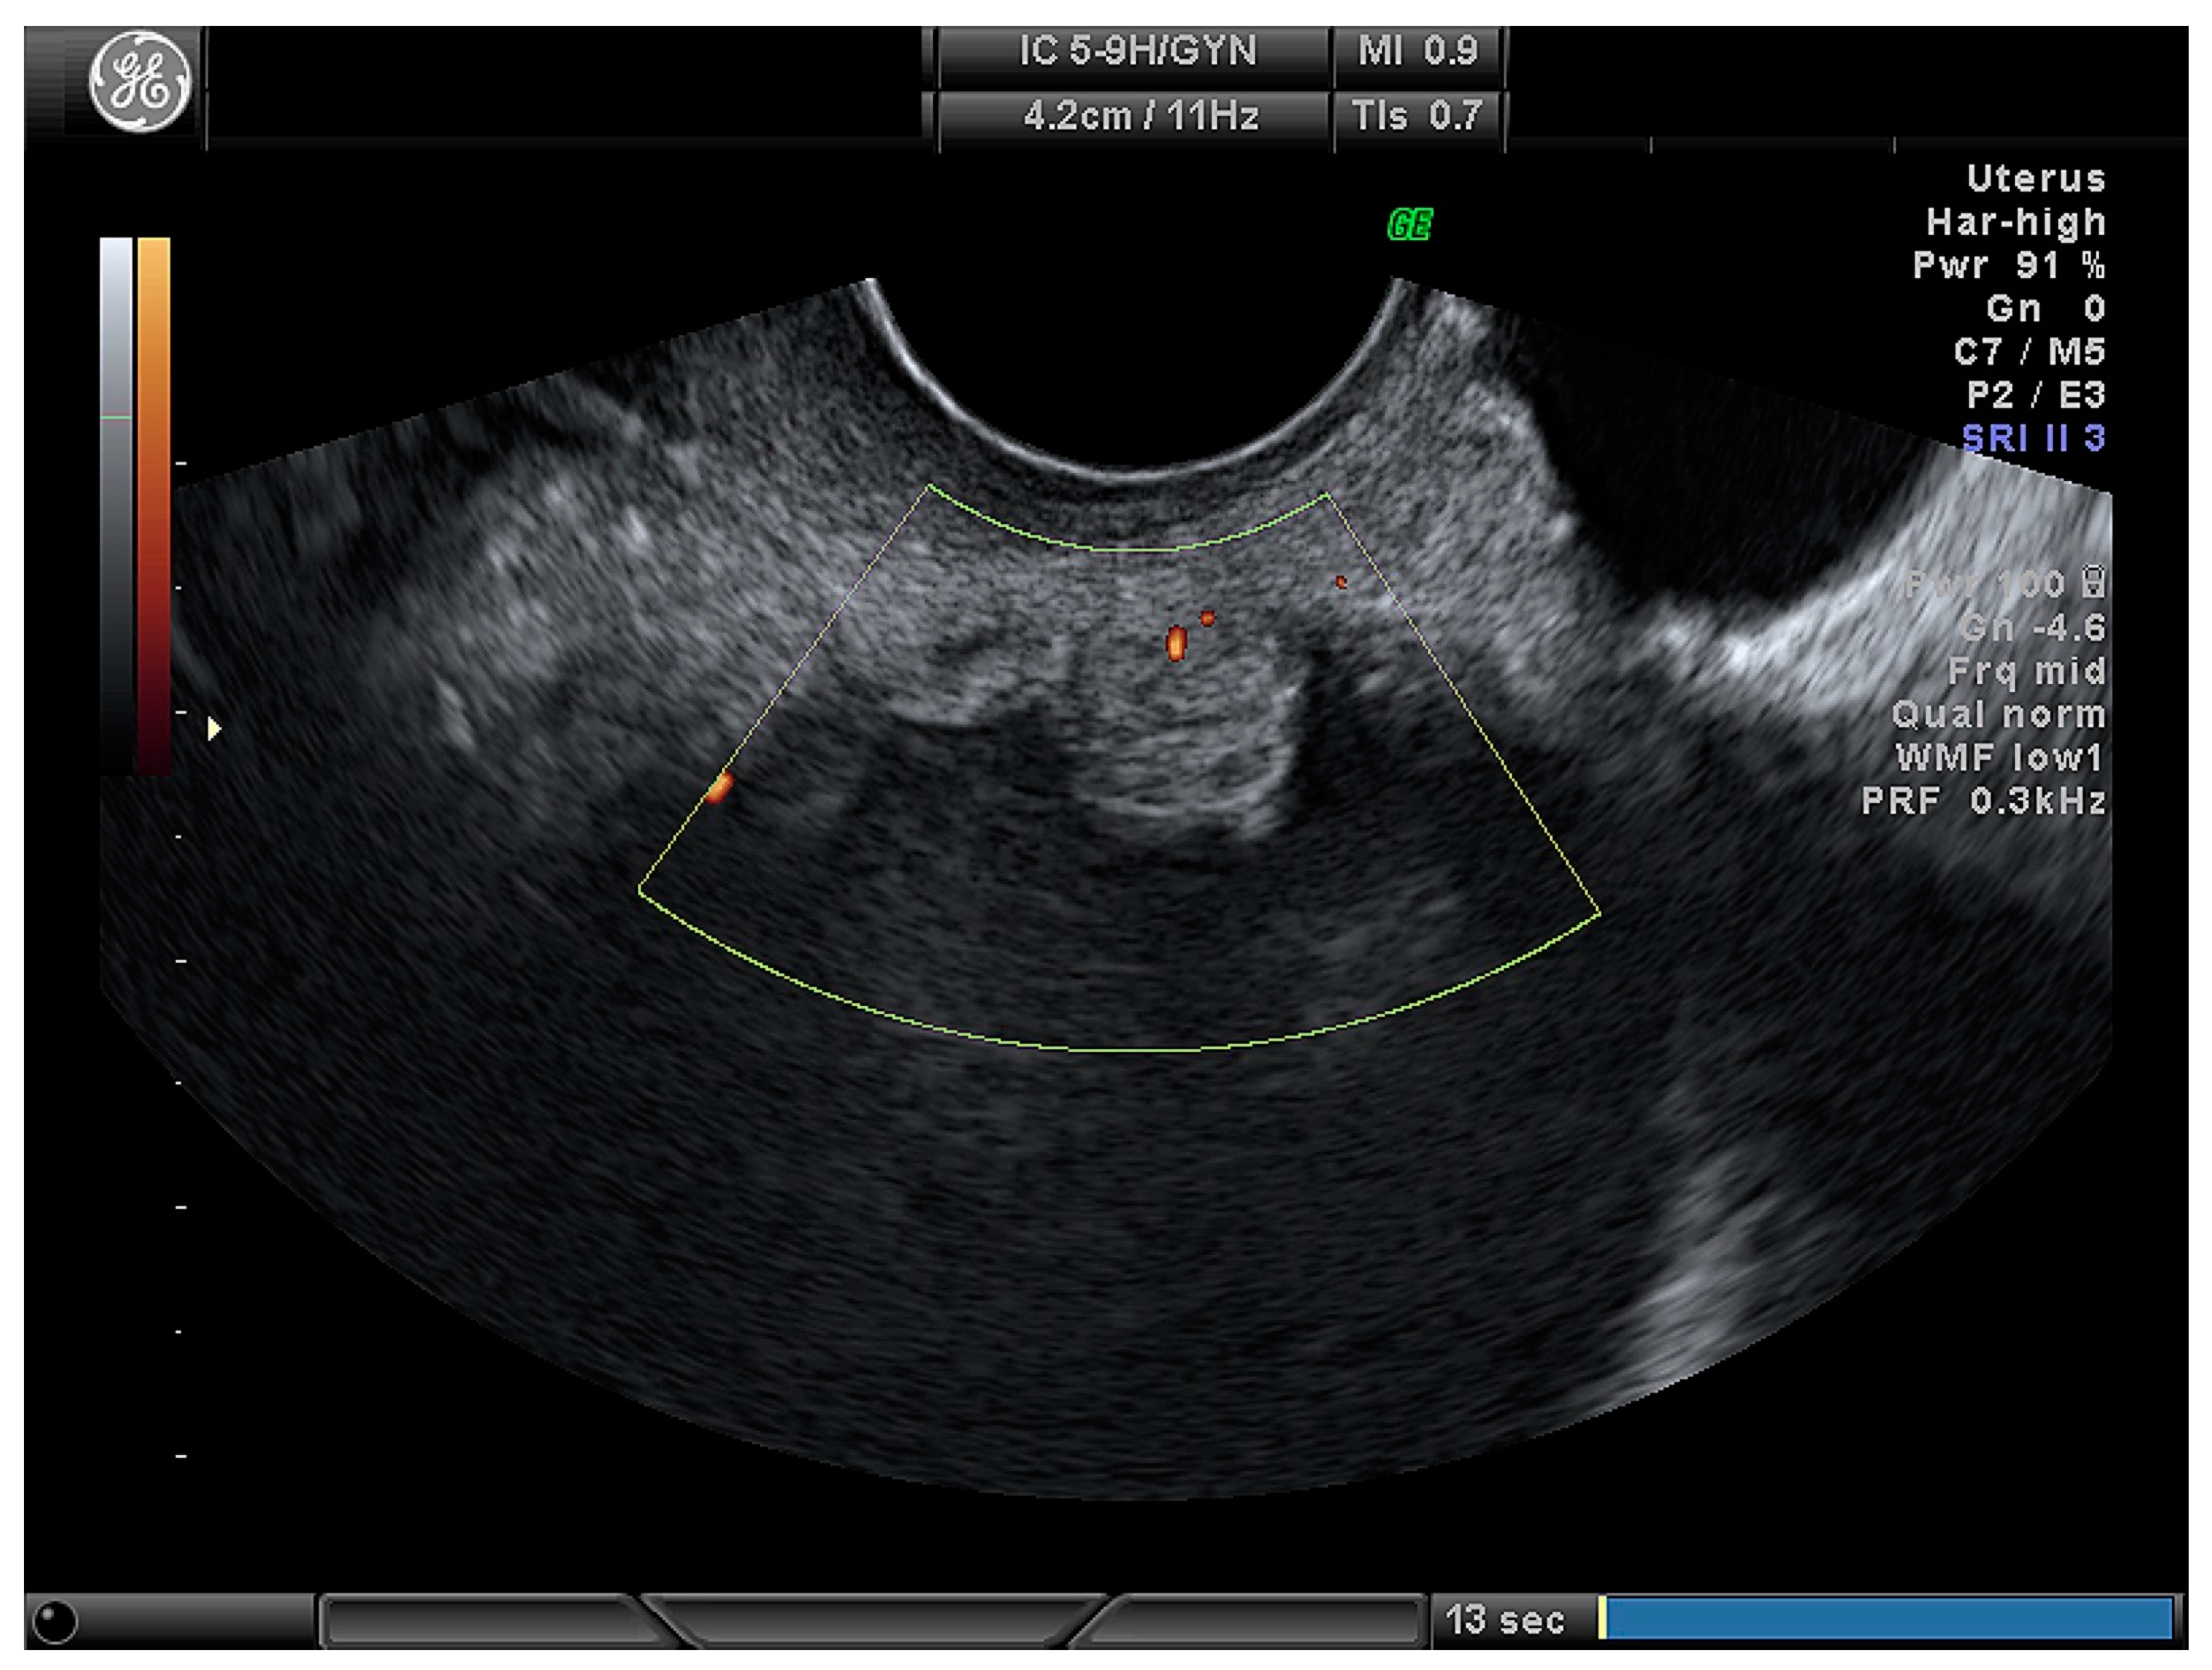

| Cystic (Figure 3) | 24 (28.2) |

| Cystic–solid (Figure 4) | 61 (71.8) |

| Number of papillary projections: | |

| None | 30 (35.3) |

| 1 | 15 (17.6) |

| 2 | 5 (5.9) |

| 3 | 2 (2.4) |

| More than 3 | 33 (38.8) |